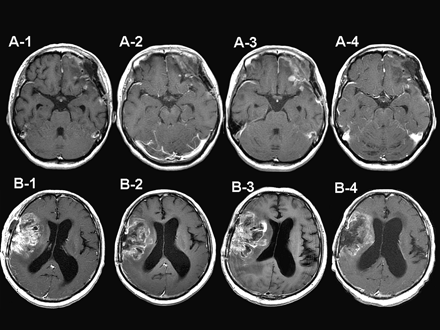

两名患者均有多发性脑膜瘤复发,并接受了重复手术和50Gy XRT分割治疗。第一例为横纹肌样脑膜瘤。BNCT也显示了质量的收缩(图A-2)随着增强体积的瞬时增加(图A-3)。增强的质量逐渐缩小,再次没有任何处理(图A-4)。第二例为间变性脑膜瘤。在这种情况下,BNCT没有显示出肿块大小的显著减小,但是在BNCT之后显示出肿瘤肿块的增强减少(图B-2)。然而,肿块在BNCT后2.5个月变大,并在肿块的大小和核心的增强方面自发地再次减小,并且病灶周围水肿减少(图B-4)。在这两种情况下,BNCT可以很好地控制局部肿块。

图示:硼中子俘获疗法治疗复发性恶性脑膜瘤假性进展的两个典型病例(BNCT)。(A-1-A-4)第一例的钆增强磁共振图像:BNCT (A-1)之前、BNCT(A2)之后48小时、BNCT(A3)之后1个月以及BNCT (A-4)之后2个月。(B-1–B-4)第二例的钆增强磁共振图像:BNCT之前(B-1),BNCT之后1.5个月(B-2),BNCT之后2.5个月(B-3),BNCT之后6个月(B-4)。